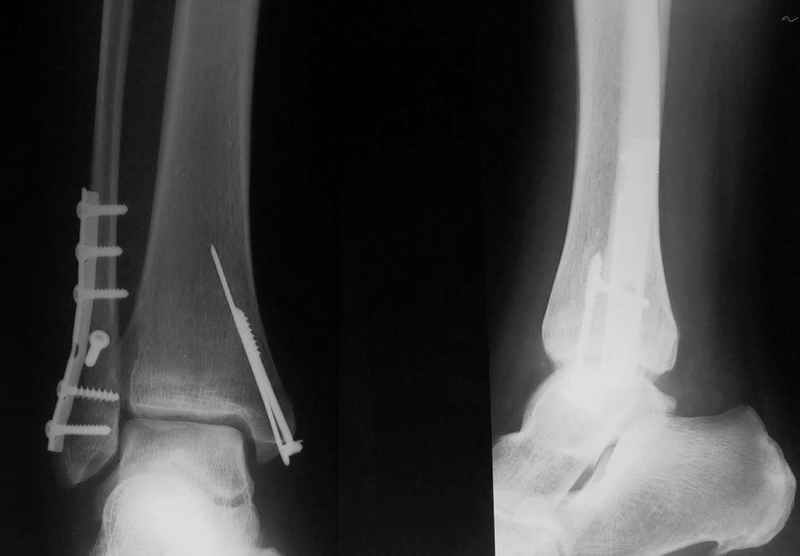

Вообщем, еще не поздно (и совершенно неопасно) снять аппарат, и сделать открытую репозицию и полноценный остеосинтез наружной лодыжки стягиваающим винтом и нейтрализующей 1\3-трубчатой пластиной... Лучше это было сделать сразу при поступлении в качестве экстренной операции, крнечно если есть возможность, а она всегда будет, если есть желание!!

Активно оперируем лодыжки с 1999г. Начинали именно с открытых, т.к. АНФ, трансартикулярная фиксация не удовлетворяли (много осложнений). Все делали ургентно по Мюллеру. Удивились, когда больные с тяжелыми открытыми повреждениями выздоравливали раньше (и полностью: через 2-3 месяца!) по сравнению с закрытыми, которых лечили в гипсе (3-5мес).

Рана по внутренней стороне г\ст сустава, ключевое дестабилизирующее повреждение м\б кости снаружи. Т.Е. внутренняя фиксация наружной лодыжки является по-сути ВНЕОЧАГОВОЙ по отношению к открытому медиальному повреждению.

Сначала: ревизия раны, многократное промывание и удаление сомнительных тканей, затем:

переодевание-перестилание-смена инструмента, остеосинтез м\б кости (наружной лодыжки), с позиционным винтом или без него, ушивание и дренирование "хирургической" раны. Затем: повторная ревизия и промывание рваной раны, остеосинтез медиальной лодыжки минимумом железа (винт и спица). Раньше всегда старалились герметично ушить с промывной системой, сейчас все чаше оставляем рану открытой и через 4-7 дней спокойно ушиваем. Естественно посевы, антибиотики... Гипсовая лонгета на 5-7 дней... после этого разрешаем наступать.

В год таких повреждений бывает 6-10. за 6 лет только два осложнения с последующим артродезированием.

Стабильность г\ст сустава обеспечивается во-первых наружной лодыжкой (ключ), во-вторых задним краем б\б кости, в-третьих связками синдесмоза и межкостной мемраной, только в-четвертых медиальной лодыжкой (дельтовидной связкой. Это классика! А пяточной кости и плюсневых костей здесь нет! зачем их фиксировать? см. вложенный файл.

Коллега!Sorry,по-моему стоит провести винт через синдесмоз,а?Вроде бы контуры г\ст не совпадают,нет?Я дал бы компрессию на синдесмоз в положении полного разгиба стопы

>>Д.Б. - Коллега!Sorry,по-моему стоит провести винт через синдесмоз,а?Вроде бы контуры г\ст не совпадают,нет?Я дал бы компрессию на синдесмоз в положении полного разгиба стопы..

1. Винт никогда не стоит проводить "через" синдесмоз. Если и проводить, то выше синдесмоза.

2. Межберцовый винт должен быть только позиционным и должен удерживать синбесмоз, а не компремировать его

3 Контуры девственны: талокруральный угол, суперпозиция, медиальное пространство. Что не совпадает?

Вообще, этот больной через 2 месяца после травмы в футбол играл.